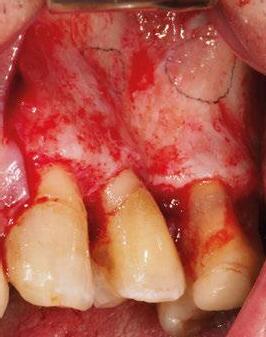

maxilectomía parcial que incluyó las piezas 24-26 y desde el reborde alveolar hasta la base del cráneo (Figuras 3 y 4). En este caso, la órbita y el globo ocular pudieron ser preservados. La reconstrucción inmediata se realizó mediante un colgajo de músculo temporal homolateral (Figura 5) y el defecto de la fosa temporal fue cubierto mediante una malla de titanio. Posteriormente, la paciente recibió radioterapia (Figuras 6 y 7). 2 años más tarde se diseñó un IS con anclaje en el arbotante nasomaxilar, zona subnasal izquierda

Figura 3. Maxilectomía parcial.

Figura 4. Defecto maxilar tras resección del tumor.